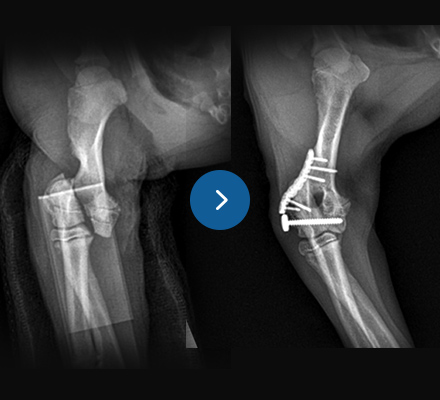

십자인대 질환

- TPLO

- 9살, 11kg, 아메리칸코커스패니엘

십자인대 질환에 대해 TPLO 수술을 진행하였습니다. 수술 직후 방사선에서 절골선이 보이지 않습니다.

정교하고 안정적인 수술로 다음날부터 산책이 가능합니다.